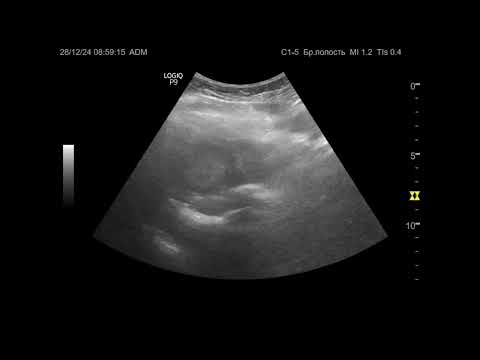

Ультразвуковая диагностика. Доктор Иогансен. Видеопримеры. Выпуск 111. Опухоль печени (5).

Представлены новые видеопримеры опухоли печени, выявленной при УЗИ. Ссылка на Дзен: Ссылка на RuTube: Ссылка на ВК видео: Ссылка на YouTube: / @dr.johansen